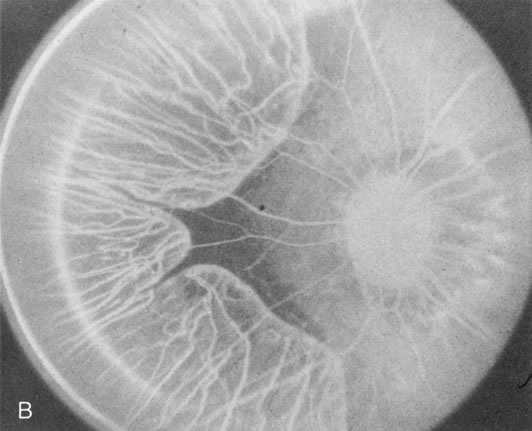

Choroideremia

In the early stages of choroideremia, before choroidal atrophy is funduscopically obvious and when the picture resembles RP, FA indicates diffuse choroidal atrophy throughout the entire retina. Only the macular area remains preserved (Fig. 4A and B).

Fig. 4. Choroideremia and choroideremia carrier. A. The choroidal atrophy in this affected male is not apparent in the fundus. B. However, the angiogram shows diffuse atrophy of the choriocapillaris with persistent visualization of the larger choroidal vessels. C. This carrier female has peripapillary choroidal atrophy and diffuse pigment mottling. D. The patchy areas of focal choroidal atrophy that occasionally occurs in carriers is evident on angiography.

The typical carrier female, with focal or diffuse pigment mottling, does not show choroidal atrophy. However, a few carrier females have a more severe form with focal areas of choroidal atrophy. The presence of these areas, and possible progression, can be documented by FA (Fig. 4C and D). These carriers exhibit a mosaicism, which is explained by the Lyon hypothesis of random X-chromosome inactivation.